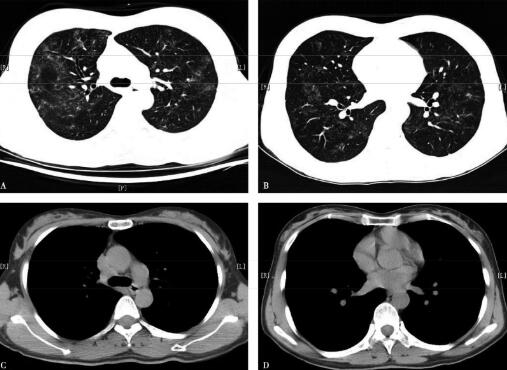

为进一步明确诊断,该患者有经胸腔镜进行肺活检的指征。患者经胸腔镜进行肺活检病理结果提示:非干酪样坏死性类上皮细胞肉芽肿(图3A:HE×100,B:HE×200)、抗酸染色阴性。肺活检组织结核杆菌PCR检查阴性、真菌和结核菌培养均阴性。至此,终于明确诊断。

图3

七、治疗方案及疗效

2009年3月给予泼尼松40mg/d[0.75mg/(kg·d)],病情好转,2009年6月9日复查胸部CT,提示双肺病变吸收明显,遗留条索影,纵隔淋巴结缩小(图4)。逐渐规律减量至停用,总疗程1.5年,外院复查胸部CT提示肺部病变吸收,纵隔淋巴结消失。

图4

评价:类上皮肉芽肿的中央部分主要是多核巨噬细胞和类上皮细胞。类上皮细胞为圆形或卵圆形,具有微细的染色质网,核质清晰,表现为水泡状的核。类上皮细胞在巨噬细胞刺激下而形成,虽有吞噬能力,但缺乏溶酶菌颗粒。类上皮细胞可以融合成多核巨细胞,周围有淋巴细胞浸润,而无干酪样病变。初期病变可见有较多的单核细胞、巨噬细胞、淋巴细胞等炎症细胞浸润,累及肺泡壁和肺间质。随着病情的进展,炎症细胞减少,非特异性的纤维化逐渐加重,多核巨细胞还常见于不易被消化的较大异物和代谢产物周围,所以类上皮肉芽肿的组织形态学并非结节病的特异性表现,也可见于分枝杆菌和真菌感染,异物或外伤的组织反应,亦可见于铍肺、梅毒三期、淋巴瘤和外源性变态反应性肺泡炎等。故临床医师需要熟练掌握上述疾病的特征性改变,有助于进一步甄别。